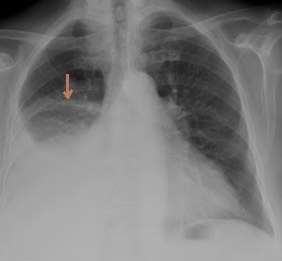

2936. Стрелка на обзорных снимках органов грудной полости отмечает